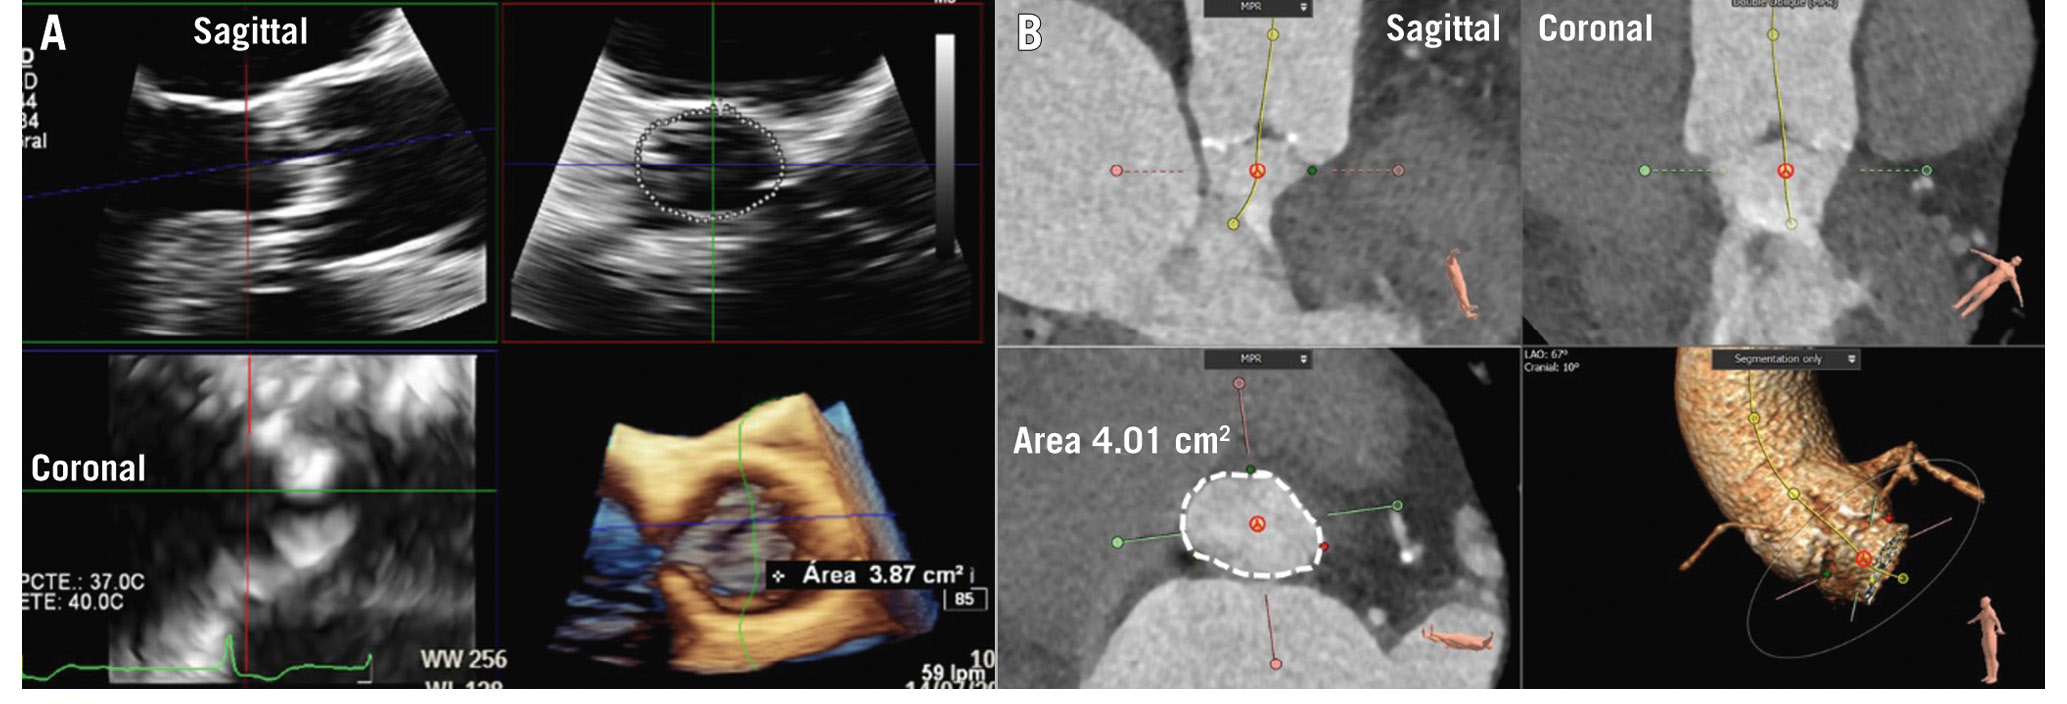

Aortic root and ascending aortic dimensions are systematically underestimated when using inner-to-inner edge measurements and may be underestimated when using two-dimensional (2D) echocardiography, as the true long axis of these structures may not be shown (Figure 3). When using 3D techniques, the cross-sectional area of the ascending aorta and sinotubular junction can be reconstructed with multiplanar reformation planes, and the measurement of the dimensions of these structures is more accurate than when measuring them from the axial views (Figure 3). The sinus of Valsalva and the ventriculo-aortic junction (aortic annulus) do not show a circular shape, and therefore, the measurement is better performed from the true cross-sectional area obtained from 3D multiplanar reformation planes. The 2D echocardiographic measurements from the left parasternal long-axis view using the leading-to-leading edge correlate with the sinus-to-sinus inner-to-inner edge measurements obtained with CT or CMR. For the ventriculo-aortic junction (aortic annulus), the cross-sectional plane obtained with 3D-imaging techniques allows the measurement of the maximum and minimum diameters, the perimeter and the area, which are key for the selection of the prosthesis size (Figure 4)678. The 2D echocardiographic diameter of the aortic annulus is usually concordant with the minimum diameter obtained with 3D-imaging techniques (Figure 4).

Figure 4. Measurement of the aortic annulus. Aortic annulus measurement with 3-dimensional echocardiography (A) and computed tomography (B). The multiplanar reformation planes are aligned across the aortic annulus bisecting the nadir points of the aortic cusps. The aortic annulus area is then planimetered (dotted line).